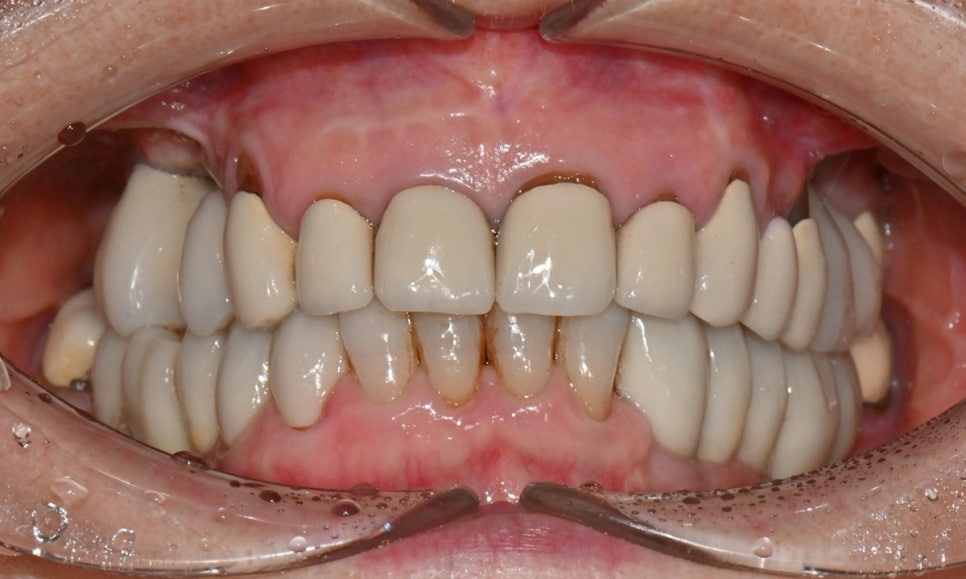

2026.1 초진 구내사진 - 연세정원치과

이번 치료에서는 기존보다 더 넓은 치아 면적을 덮는 보철이 필요했고, 특히 가운데 앞니 보철의 안쪽에서 마모 양상이 관찰되어 크라운 제거 후 추가적인 치아 삭제가 불가피할 가능성이 있었습니다. 이에 따라 치료 전부터 신경 치료 가능성에 대하여 충분히 설명을 드린 후 치료를 시작하였습니다. 또한 이렇게 오래된 보철물을 제거해보면, 내부에 이차우식이 발견되는 경우도 흔하기 때문에, 추가적인 레진 치료 가능성에 대해서도 미리 안내드렸습니다.

이처럼 여러 개의 앞니 보철 교체가 필요한 경우에는 현재 상태에 대한 설명뿐 아니라, 최종 보철의 디자인에 대해 환자분과 충분한 소통과 상담이 매우 중요합니다. 이 환자분의 경우 기존 앞니가 전체적으로 너무 크고, "남성적인(masculine)" 인상을 준다고 느끼셨고, 색상 또한 더 밝게 교체하고 싶어하셨습니다.